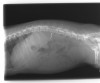

術式は片側椎弓切除によるもので、白く横長の部位が露出した脊髄(矢印)である。この症例では突出した椎間板物質そのものの摘出も行った。本症例は術後経過良好で術後6日目に退院した。